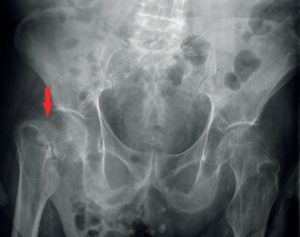

Gossypiboma, appelé aussi textilome : une compresse oubliée en peropératoire

Description du cas Mr J., 86 ans, est hospitalisé dans le service de médecine aiguë gériatrique pour un syndrome confusionnel hypervigile avec troubles du comportement à type d’hétéro-agressivité, inversion du…